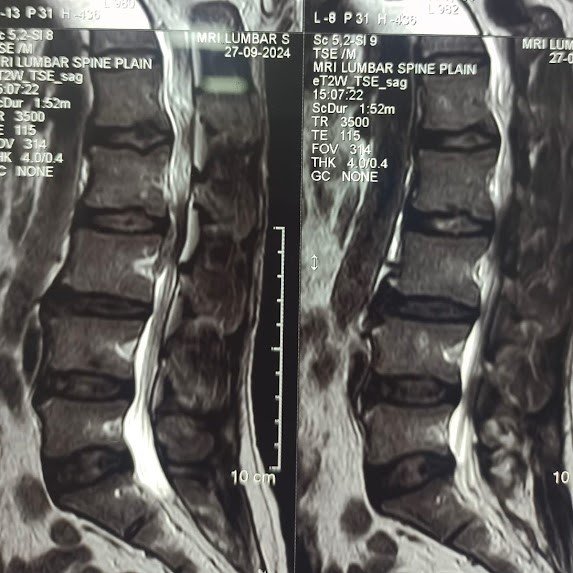

Special Cases Cervical Disc Prolapse with Spinal Cord Compression Condition:Cervical disc prolapse in which the herniated disc compresses the nerve roots and spinal cord, often associated with spinal cord edema. Symptoms:Neck pain, numbness in hands, weakness, difficulty in walking, and coordination problems. Treatment:Anterior Cervical Discectomy and Fusion (ACDF) – The…